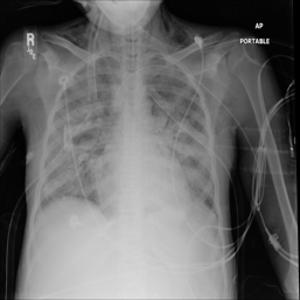

Ushbu platforma ko‘krak qafasi rentgen tasvirlarini sun’iy intellekt yordamida tahlil qilishga mo‘ljallangan bo‘lib, COVID-19, o‘pka fibrozlari, pnevmoniya hamda sog‘lom o‘pka to‘qimalarini to‘rt sinf bo‘yicha aniqlash uchun maxsus o‘qitilgan konvolyutsion neyron tarmoq (CNN) modelidan foydalanadi. Tizim tasvirni oldindan qayta ishlash, shovqindan tozalash va kontrastni kuchaytirish kabi raqamli algoritmlar asosida yuqori aniqlikdagi diagnostik xulosani taqdim etadi.